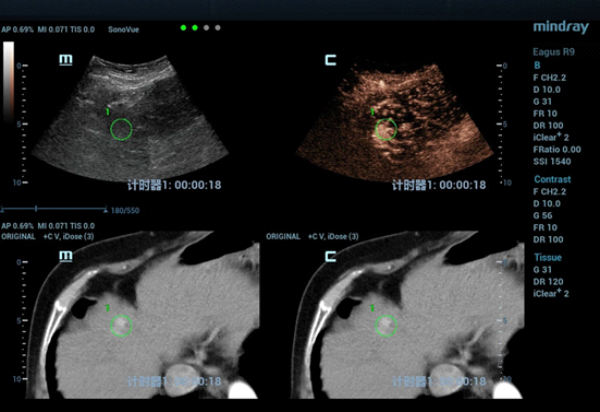

The S4 tumor seen on abdominal CT could not be demonstrated on conventional gray-scale ultrasound imaging. On contrast-enhanced ultrasound (CEUS) the lesion demonstrated hypervascularity in the arterial phase (Fig. 2) with iso-enhancement in the portal and late phases (Fig. 3).

The patient was scheduled for ultrasound-guided microwave ablation (MWA), however, as the lesion could not be seen on conventional ultrasound, fusion imaging combining ultrasound imaging and contrast-enhanced CT (Clip 1, Figs. 4-7) was used to ensure accurate positioning of the microwave antenna.